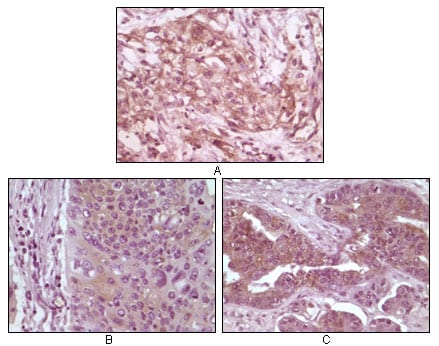

分类: 科研抗体货号: 20085别名: MGC10442应用: IHC反应种属: Human

分类: 科研抗体货号: 20090别名: MGC10442应用: IHC反应种属: Human